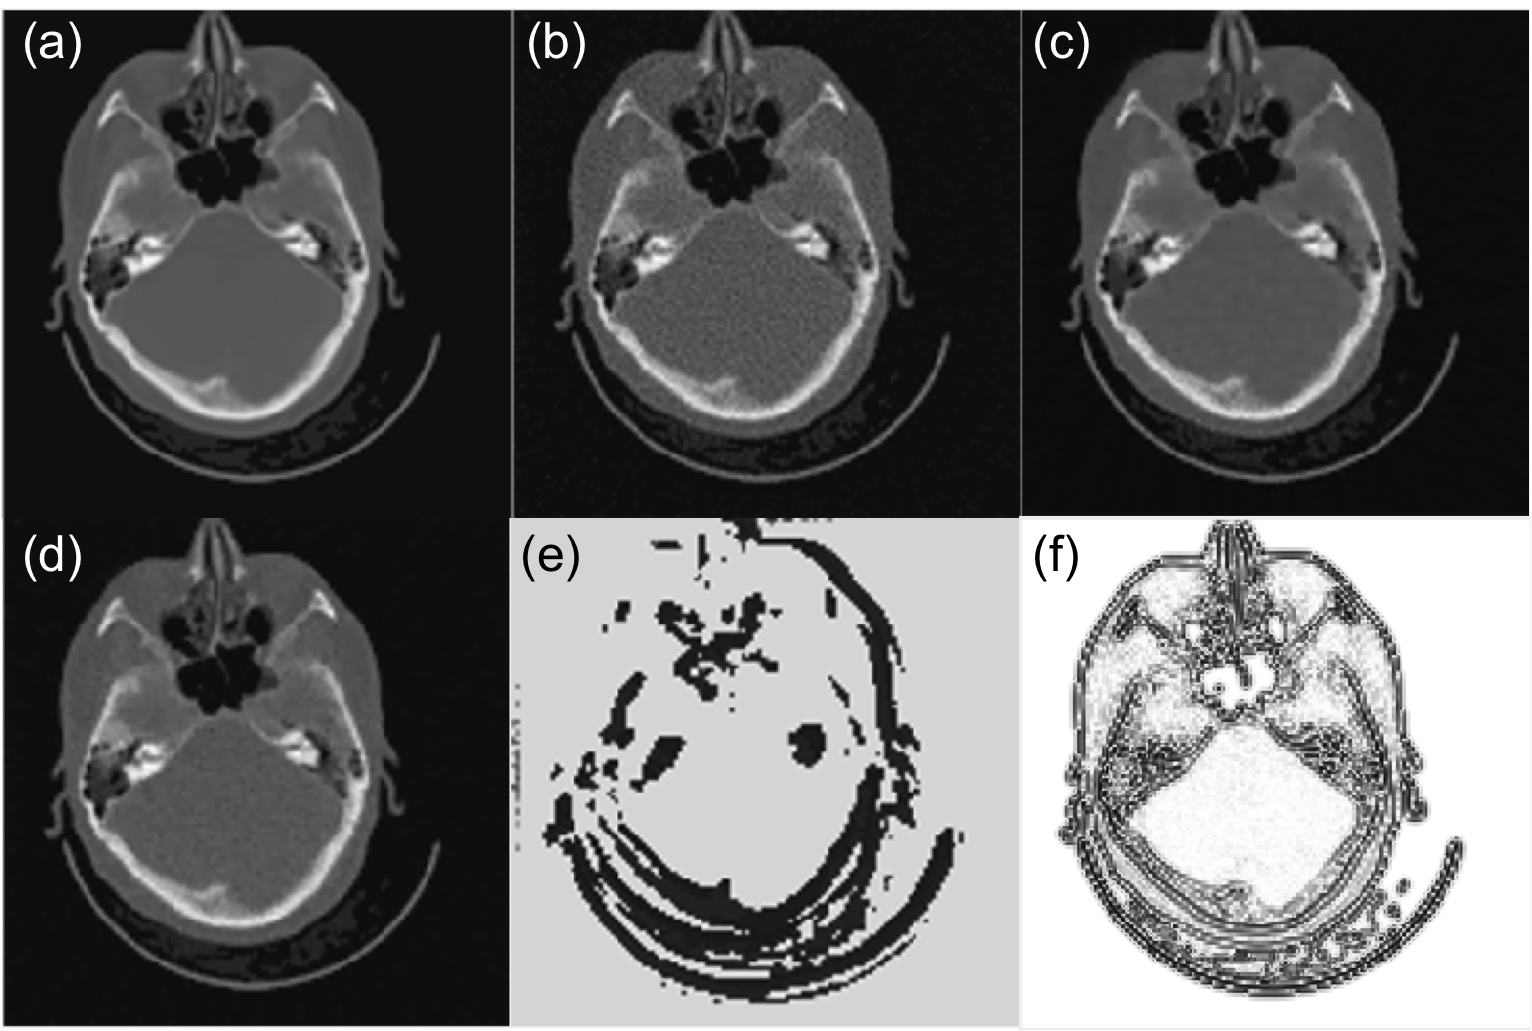

To observe this process in detail, we select a test case that is not used in training. Fig. 5(a)-(c) present reconstructed CT images at step 1, 4, and 7. It is clear that the image quality is improved with the parameter tuned. Quantitatively, we compute the relative error at different steps and plot it in Fig. 5(d). A monotonic decay trend is observed, indicating the effectiveness of parameter tuning.

Fig. 6 is a case that is used in training, whereas Fig. 7 is the same one in Fig. 5, which is not included in training. Since we arbitrarily set initial values of , which is too small in these two cases, the resulting images contain a lot of noise (Fig. 6(b) and 7(b)). After the parameter is tuned by PTPN, the image quality in both cases is substantially improved (Fig. 6(c) and 7(c)).

We compare the results with those under manually tuned parameters. Since it is impractical for one to adjust the parameter for each individual pixel, we consider a special context that the parameter is a constant throughout the image and we manually adjust this parameter value for the best image quality. The appropriate parameter values are for Fig. 6 and for Fig. 7. Fig. 6(d) and 7(d) depict images reconstructed under these parameters in the two cases, respectively. It is found that the images still contain a certain amount of noise and the quality is inferior to those with parameters tuned by PTPN.

As for the parameter maps tuned by the PTPN shown in Fig. 6(e) and 7(e), it is observed that PTPN deliberately reduces parameter values most around image edges. This is understandable. Reducing parameters at those pixels decreases the amount of regularization in those areas, which is beneficial in terms of preserving image edges.

Interestingly, for the simple problem in Eq. (2), it is possible to derive the optimal parameter map . As such, let us take the gradient of the objective function and set it to zero at : . This implies that the optimal parameter map is

The numerator in this expression is more or less an image of noise that is obtained by back-projecting the residual error in the projection domain to the image domain. Here, we neglect the image structure of the noise and plot the image in Fig. 6(f) and 7(f) for the two cases, respectively. The images shows that is small along the image edges. Comparing subfigures (e) and (f) in Fig. 6 and Fig. 7, the similarity between corresponding pair of images implies that PTPN can intelligently adjust towards the optimal parameter maps. Note that this intelligence is purely developed by the PTPN itself through the reinforcement learning process. Except providing rewards for an action, we do not explicitly give any information regarding how to tune the parameters.